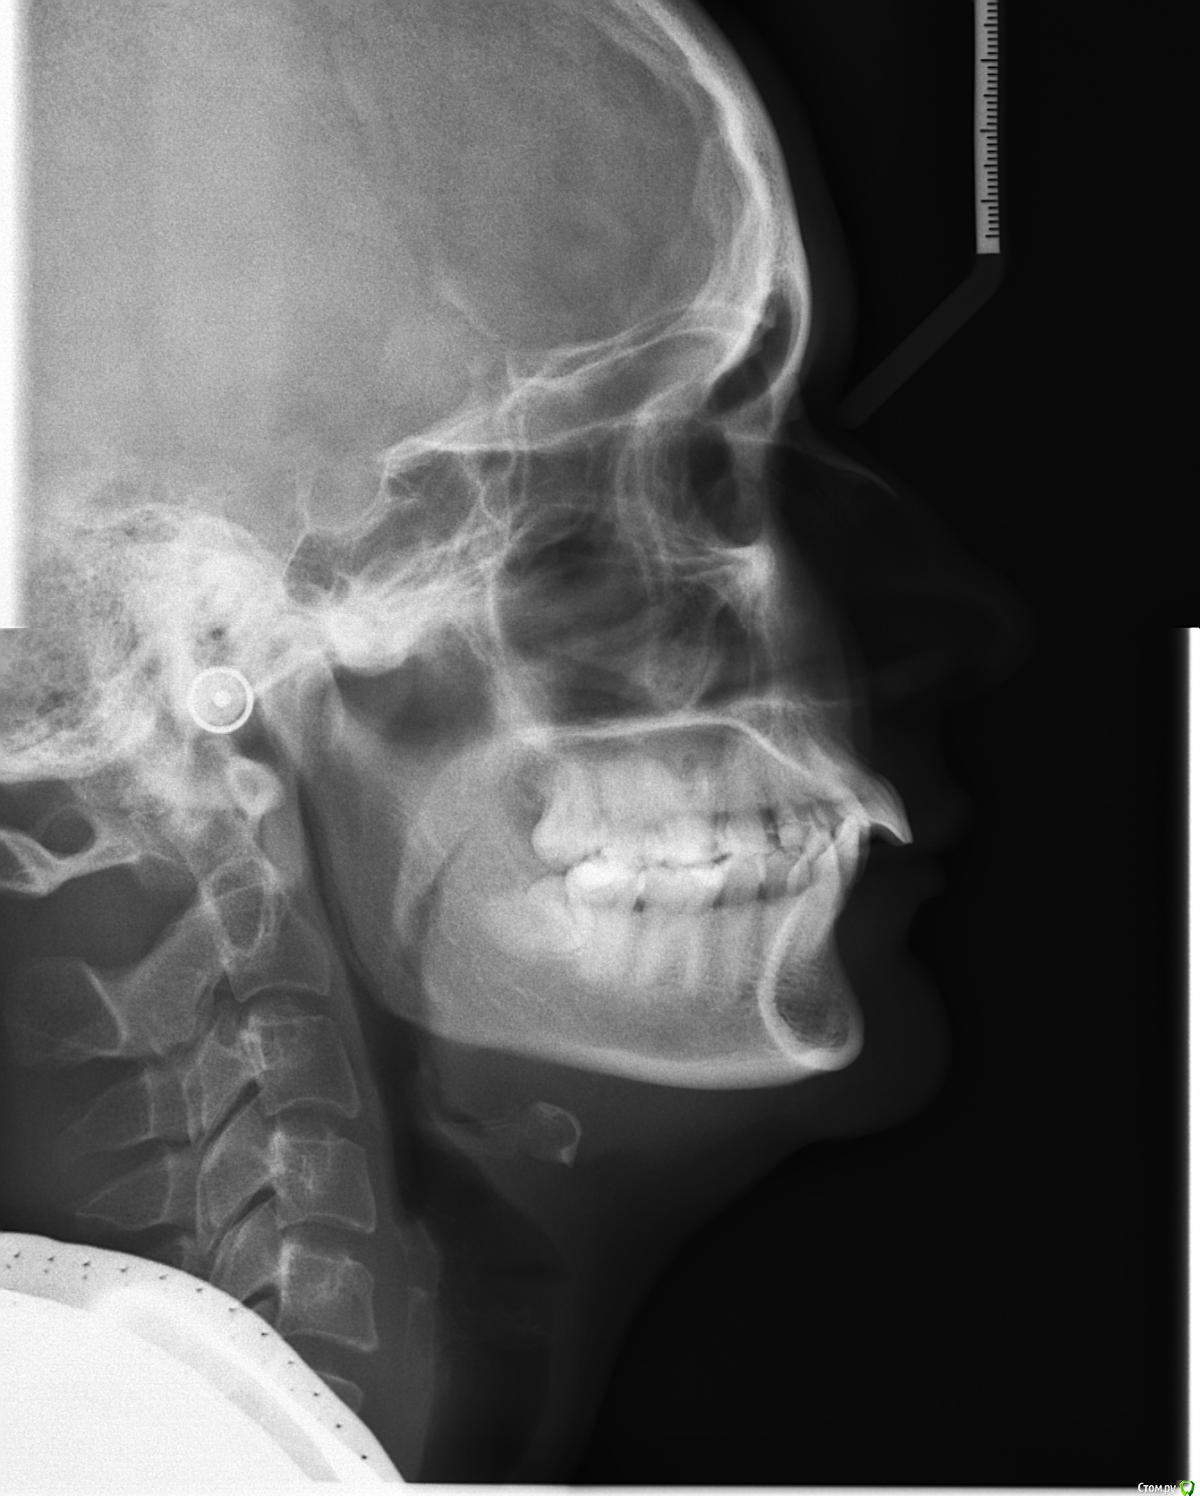

losenok83 Опубликовано 11 мая, 2016 Поделиться Опубликовано 11 мая, 2016 Здравствуйте! Мне 32 года. Год в брекетах. Уже больше 3-х месяцев беспокоит боль в в суставе, при открывании рта, иногда при жевании. До брекетов у меня хрустел сустав с левой стороны, сейчас хрустит с обеих сторон+ закладывает периодически уши. Лечусь с удалением 4-рок на ВЧ. Справа 4-ка была удалена в детстве по орт.показаниям , слева вначале нынешнего лечения. Не связана ли боль в суставе с удалением 4-рок? Действительно ли нужно было их удалять? Не нужно ли было выдвигать нижнюю челюсть вперед спец. аппаратами? И что можно сделать сейчас? Фото и снимки до лечения. Ретинированная 8-ка удалена. Ссылка на комментарий

losenok83 Опубликовано 4 сентября, 2016 Автор Поделиться Опубликовано 4 сентября, 2016 Здравствуйте, очень нужна ваша помощь снова! Я обошла много ортодонтов в своем городе на предмет дальнейшего лечения. В конце концов мое самочувствие более менее менее улучшилось только после ортотика. В дальнейшем мне сказали ортодонт поставит мои зубы на такую высоту. Скажите пожалуйста это правда возможно, на такую высоту вытянуть свои верхние и нижние зубы? И еще изначально этот ортодонт планировала что в этом ортотике Н,Ч, выйдет вперед , а потом ее расширят. Поскольку этого не произошло, сказала что просто раздвинут место для раннее удаленных 4-рок на В,Ч. пружинами. А я очень боюсь, что в результате зубы будут торчать вперед как раньше.Разве нет? Расчет ТРГ на данный момент лечения. И вид челюстей в ортотике. Ссылка на комментарий

Yana guapa Опубликовано 6 сентября, 2016 Поделиться Опубликовано 6 сентября, 2016 1. где сам снимок трг? 2. вы из ростова но расчет я так понимаю делал московский врач а не ваш? 3. мне трудно комментировать данное лечение, потому что мой план лечения отличался бы ... но на мой взгляд - высота завышена, и явно далека от терапевтической нормы... Нужен снимок ТРГ а не расчеты чужие . (с удовольствием послушаю мнение коллег) 4. не первый раз вижу расчеты с такой фамилией, заинтересовала графа - "АНГУЛЯЦИЯ резцов вч и нч" - комментарий ПРОТРУЗИЯ. (это к коллегам вопрос) интересный расчет))) 2 Ссылка на комментарий